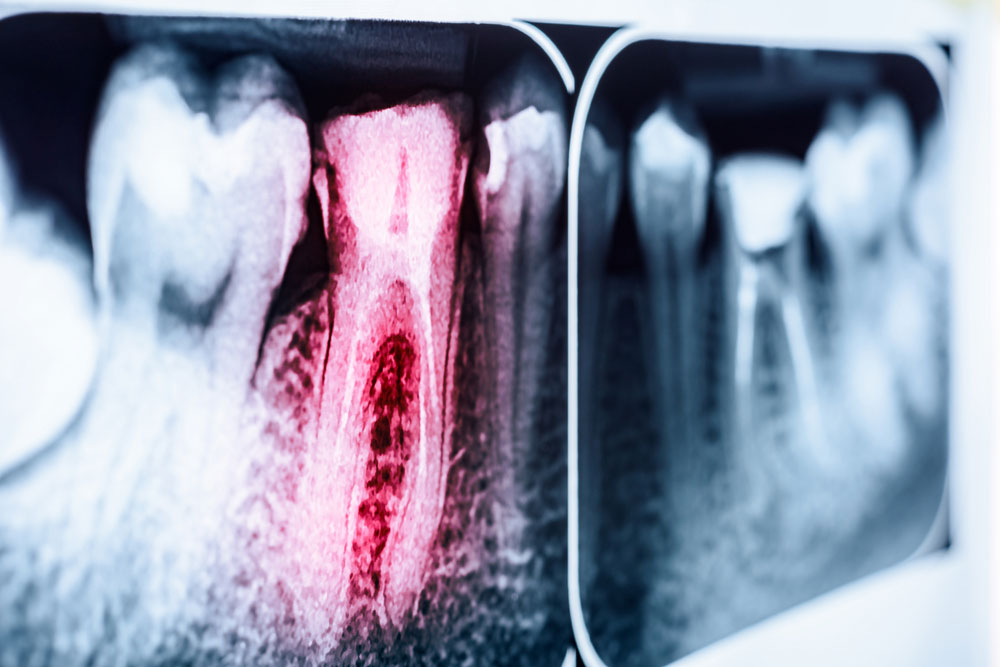

Canal treatment implies removal of inflammatory or dead dental pulp that causes toothache, abscess and cyst formation from root canals and completely filling the resultant space with a non-hazardous, tissue-friendly substance.

The dental “pulp” is the part of tooth, where neurovascular bundle – a layer that ensures viability of tooth – is located beneath enamel and dentin layers. This compartment is referred as “pulp chamber” on the crown and it extends down to root of tooth. If the pulp gets inflamed due to a reason whatsoever, dental pulp is removed and canals should be cleaned and filled.

Pulp, which is neural tissue of tooth, is not able to make self-recovery in deep caries or deep tooth fractures and viability of tooth is lost. Non-viable tooth transforms into an infectious focus. At this stage, canal therapy should immediately be carried out by dentist. If canal therapy is not performed, infection may spread down to tissues at the tip and periphery of the root. It causes loss of bone at the locus by inflaming the jaw bone that surrounds root of the tooth. Canal treatment of teeth at this phase may require more complicated and longer procedures. In case of negligence, disappointing results may occur, even including loss of teeth.